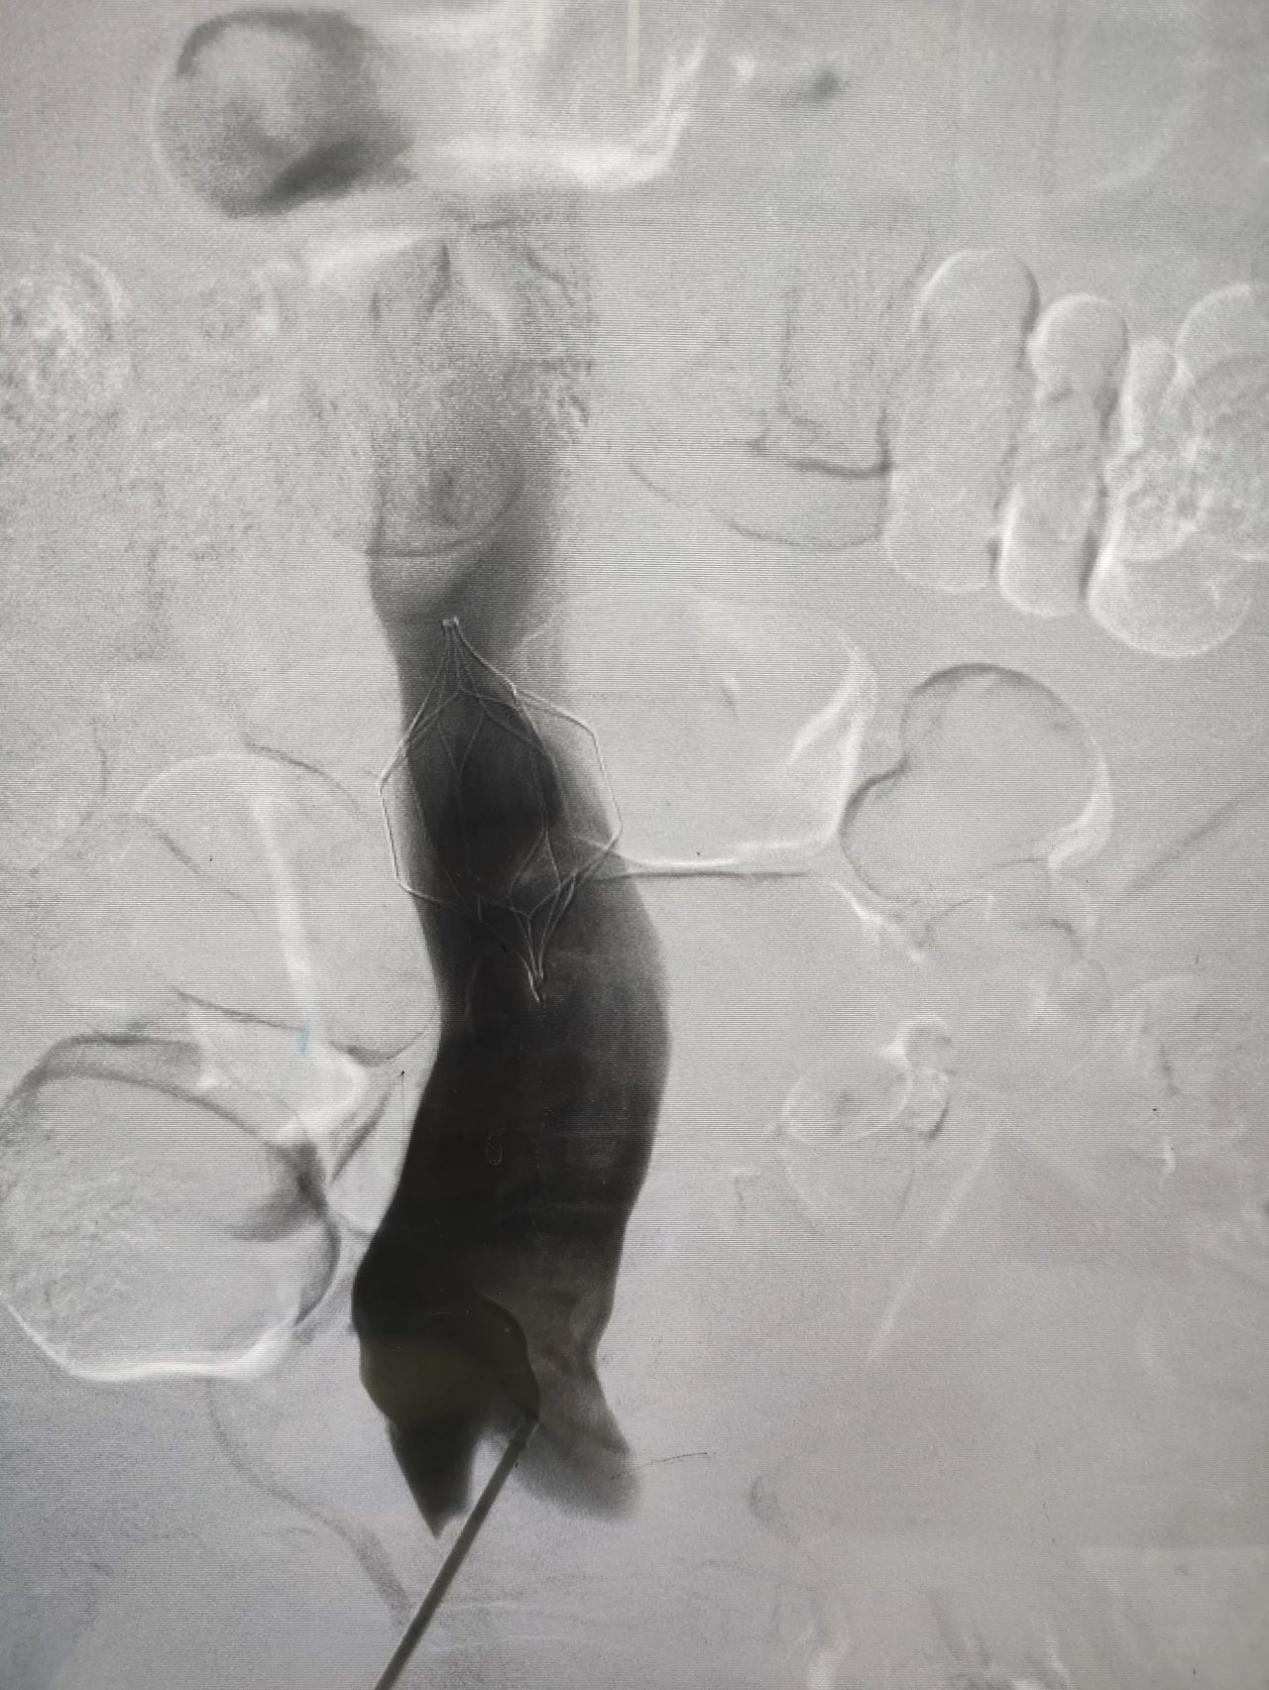

患者男性,69岁,2024年8月12日以“右侧下肢肿胀1周”在综合外科二病区就诊,后以“右下肢深静脉血栓形成”积极收住院治疗。次日查房时发现,患者血氧过低(约60%),我科援藏专家谢文涛主任考虑患者存在肺栓塞可能,立即主持科内术前讨论后建议立即行肺动脉造影介入治疗。经过40分钟的紧急手术治疗,左肺动脉主干血栓完全清除,为预防后期再次出现肺栓塞,同时下腔静脉置入可回收滤网。患者自身症状明显缓解,患者及家属对治疗效果非常满意,并于两周后,8月28日再次入住综合外科二病区,顺利取出可回收滤器。